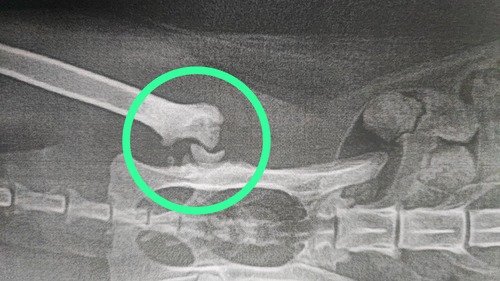

Aqui algumas de suas fraturas:

Vitória (nome que demos a ela por sua força de sobreviver a uma queda de 18 metros!) chegou com múltiplas fraturas, feridas graves e muita dor. Passou por exames, ficou internada, foi operada e agora luta para se recuperar. Ela precisou de cirurgia com barra de titânio, tratamento de feridas expostas e acompanhamento intensivo.